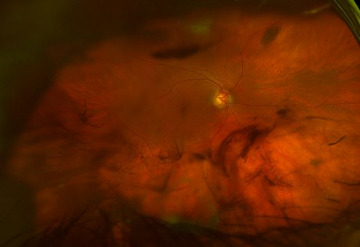

The slit-lamp examination of the right eye was remarkable for conjunctival injection, mild corneal haze and endothelial pigment, iris transillumination defects, 3+ cells and flare and a microhyphema with pigmented cells. The PCIOL was displaced inferiorly; the superior haptic was visible through the pupil and the inferior haptic was in contact with the posterior iris causing an inferonasal transillumination defect (Figure 1). The left eye was white and quiet with a superior filtering bleb. Intraocular pressures with Goldmann applanation tonometry were 18mmHg in the right eye and 11mmHg in the left eye. Dilated fundus examination revealed a 4+ dense vitreous hemorrhage that obscured the view of the retina in the right eye and a normal, intact retina in the left eye.

At two-weeks follow-up, the patient reported improved floaters in the right eye. His VA was 20/50 in the right eye. The anterior chamber reaction had improved to only trace flare and 3+ cells which were primarily pigmented. The intraocular pressure was 22mmHg in the right eye and 11mmHg in the left eye. Dilated fundus examination revealed presence of residual grey vitreous strands and a resolving vitreous hemorrhage inferiorly (Figure 2). The patient was instructed to reduce prednisolone acetate 1% to four times daily, continue using cyclopentolate 1% three times daily, and to return for follow-up in three weeks.